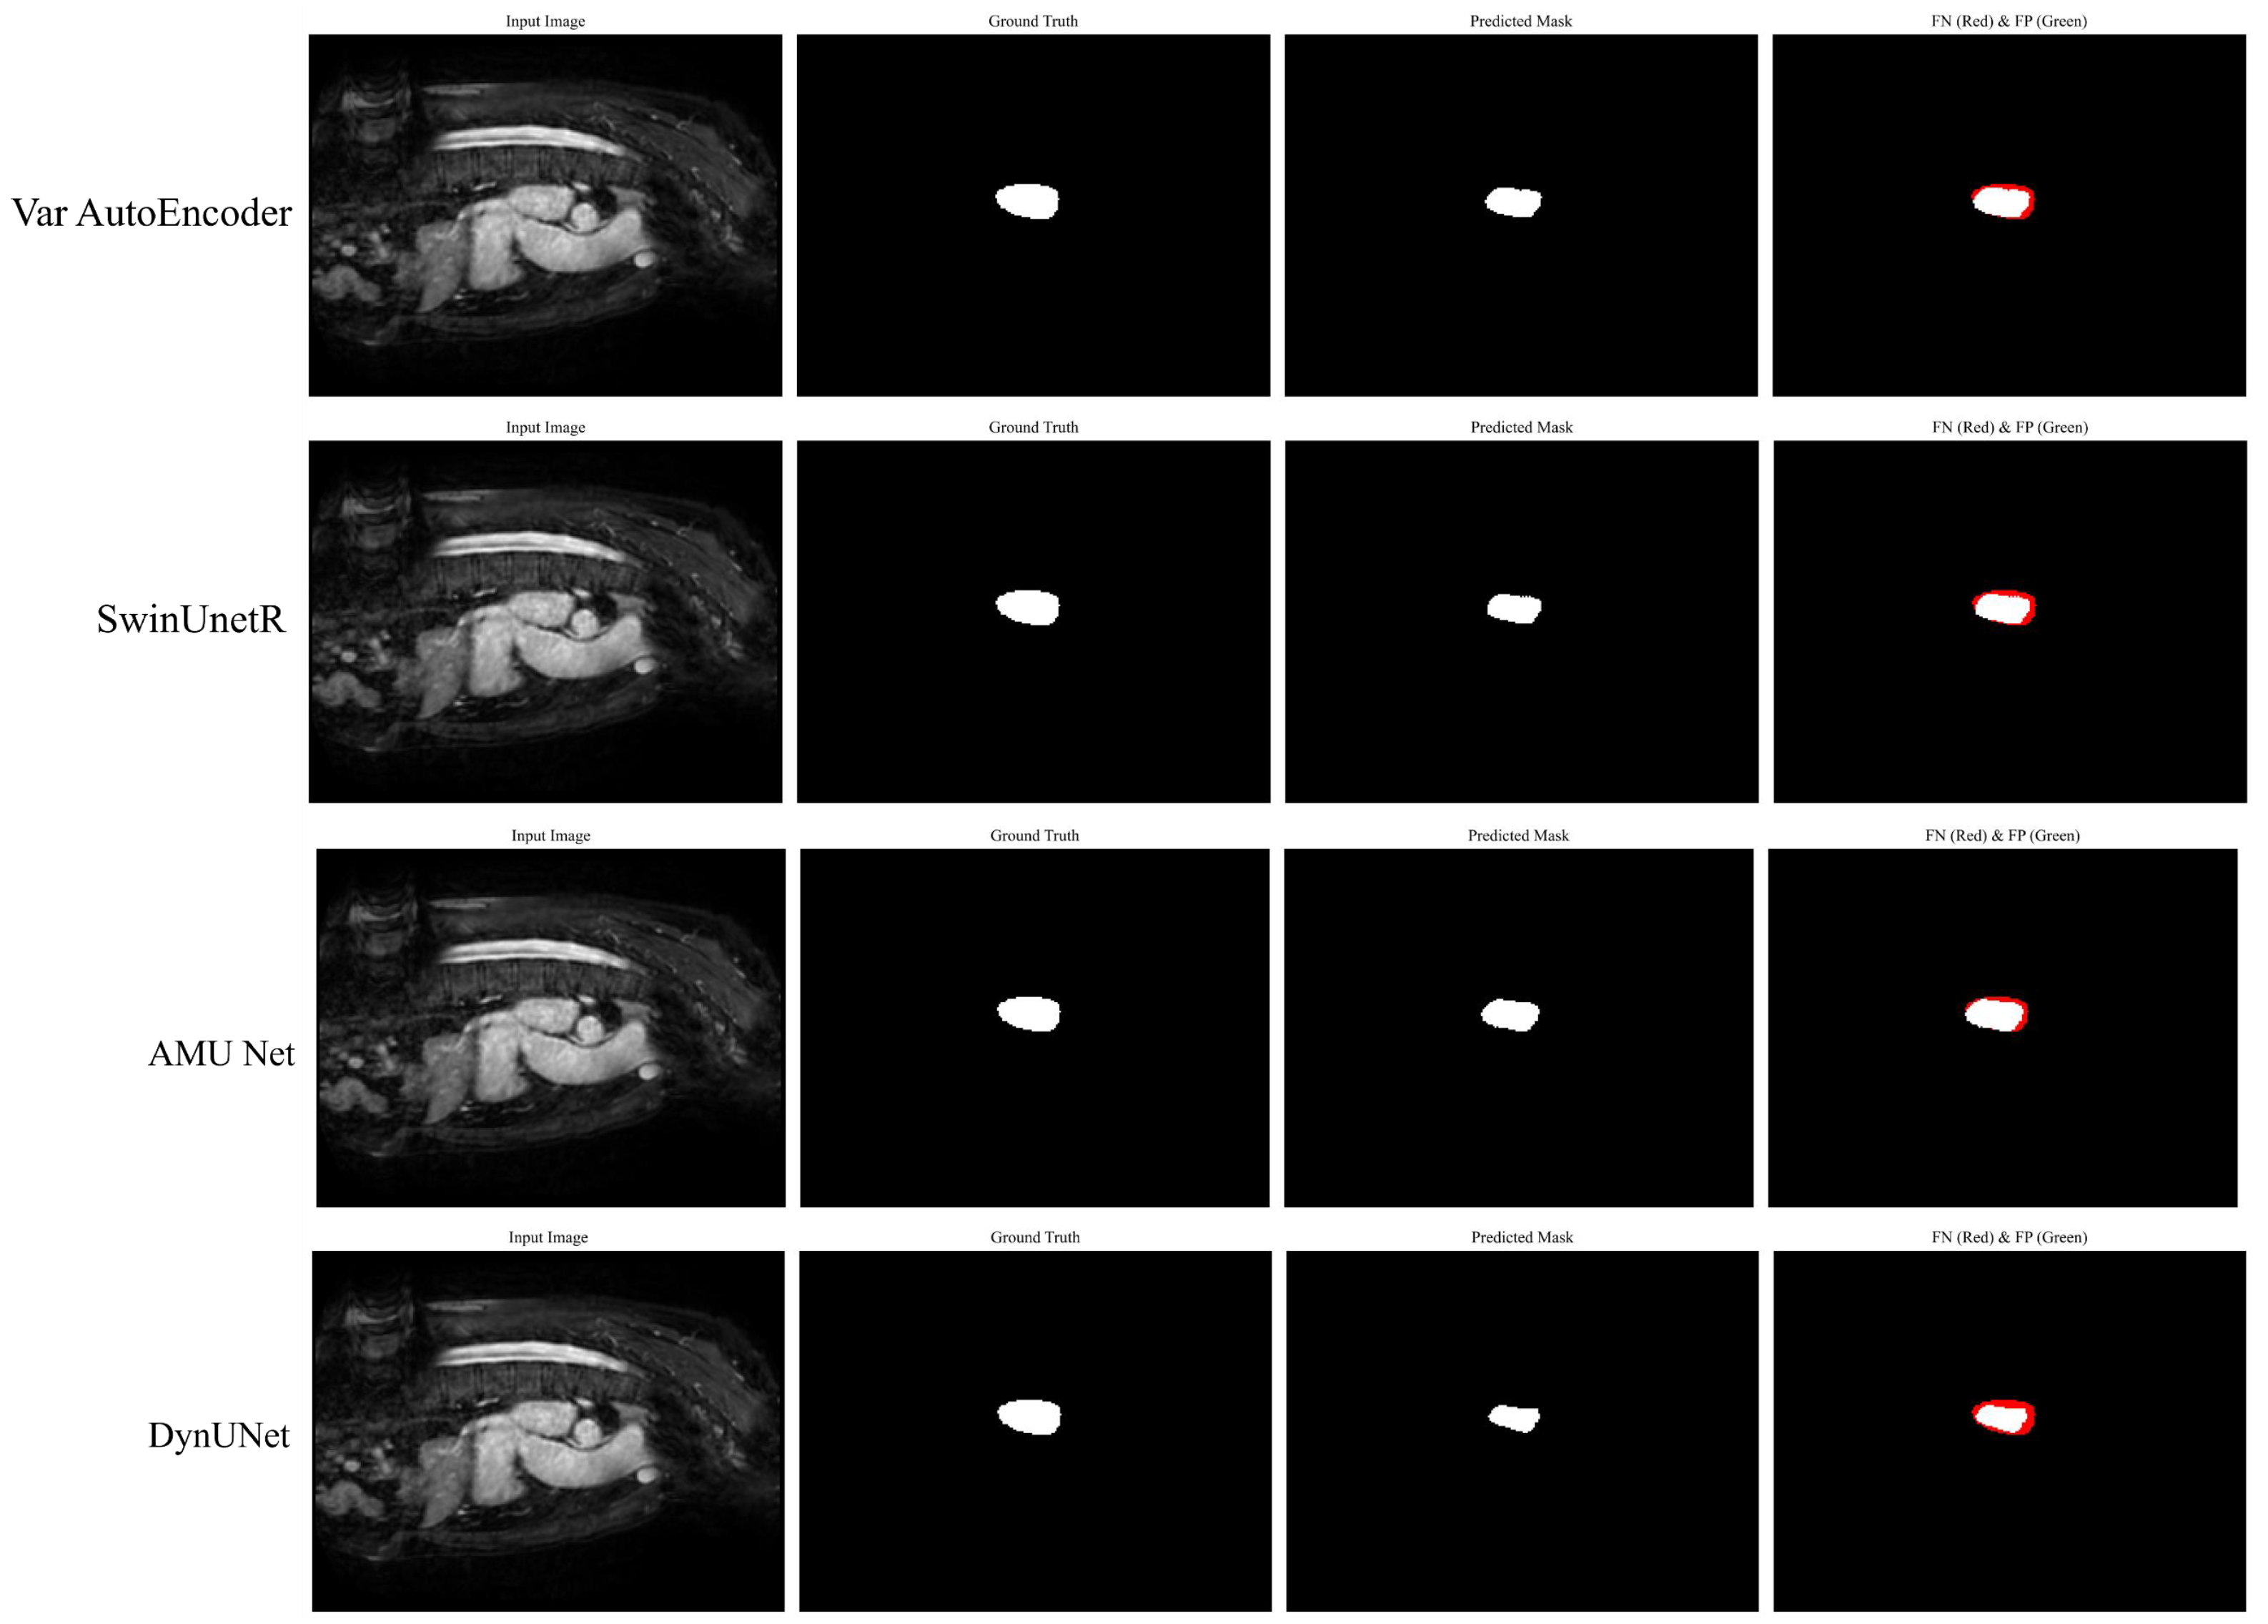

3.5. Qualititative Analysis

| Model Name | Dice Score | mIOU | Precision | Recall | Parameters (M) | FLOPS (GMac) |

|---|---|---|---|---|---|---|

| SegResNet [40] | 91.25 | 90.53 | 92.48 | 90.50 | 11.76 | 196.05 |

| DynUNet [41] | 92.50 | 91.72 | 93.07 | 91.59 | 5.65 | 113.08 |

| SwinUNETR [42] | 92.81 | 91.93 | 93.26 | 92.14 | 62.19 | 328.72 |

| UNETR [43] | 90.37 | 89.15 | 91.65 | 91.18 | 87.63 | 679.24 |

| VarAutoEncoder [44] | 92.66 | 91.22 | 92.14 | 91.07 | 135.81 | 44.08 |

| VNet [45] | 91.62 | 90.87 | 92.21 | 90.94 | 45.6 | 324.16 |

| DDRNet-39 [46] | 90.71 | 90.14 | 90.97 | 91.07 | 32.38 | 140.62 |

| PIDNet-L [47] | 91.18 | 91.58 | 92.02 | 92.39 | 36.94 | 275.87 |

| Mask2Former [48] | 92.88 | 91.42 | 93.37 | 92.55 | 215.47 | 403.31 |

| SegViT [49] | 92.75 | 91.39 | 93.22 | 91.64 | 138.24 | 432.6 |

| AMU-Net | 93.35 | 92.69 | 94.12 | 92.78 | 94.78 | 804.15 |